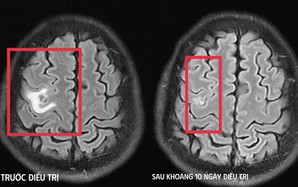

Viêm xoang bướm do nấm âm thầm tấn công người bệnh

(NLĐO ) - Bệnh viêm xoang bướm do nấm có triệu chứng mơ hồ, không điển hình, dễ nhầm với viêm xoang mạn thông thường.